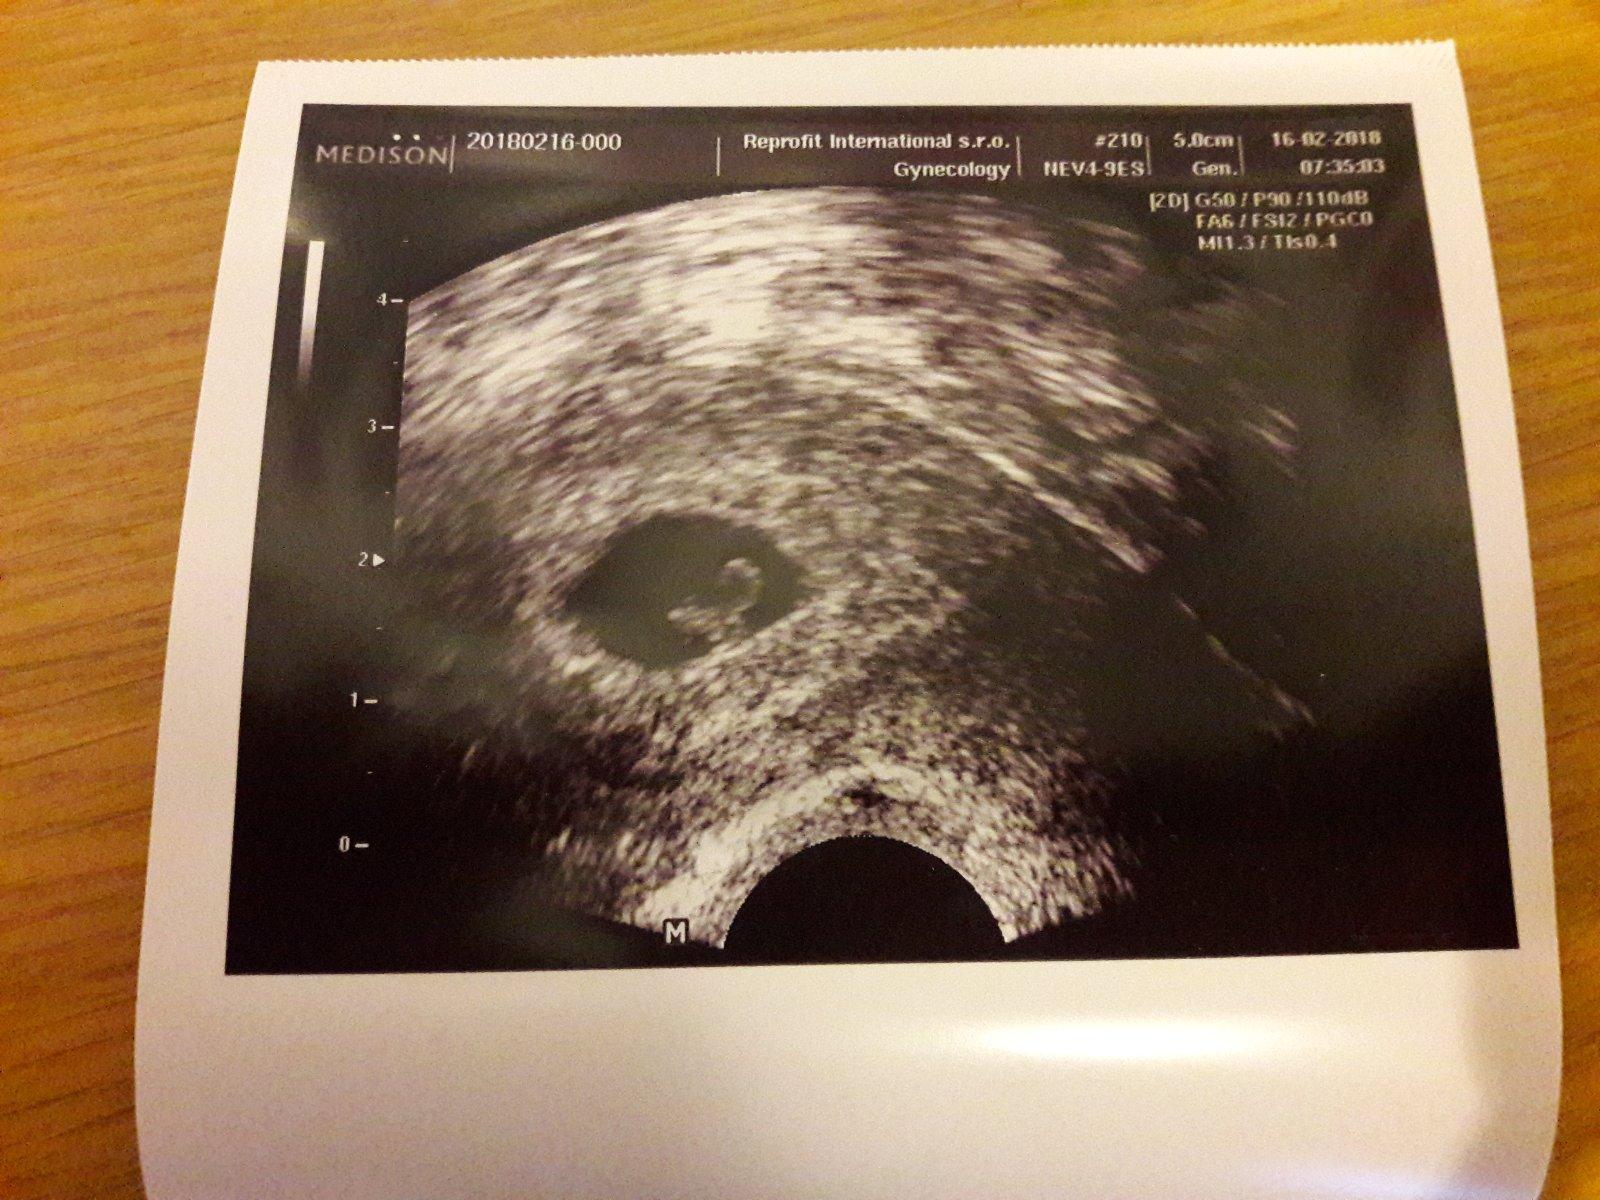

Ahoj devcata, tak dnesni kontrola probehla dobre 🙂, dle doktorky probihajici 6. tyden a bylo uz i ❤ 🙂. Tak doufam ze se bude pidizvikovi dobre darit i dal 🙂